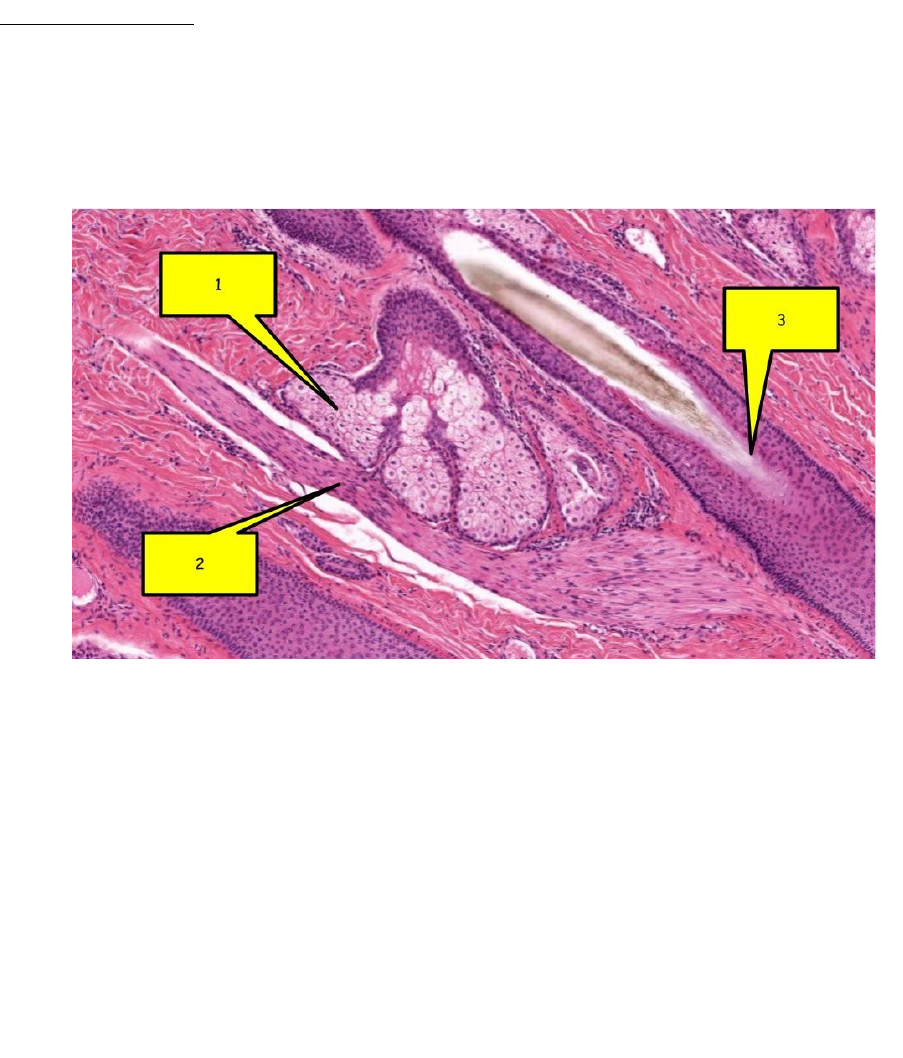

<p>PELE E ANEXOS</p><p>1) Analise a imagem abaixo e assinale a alternativa correta:</p><p>a) São anexos da pele espessa: 1- Glândula sebácea; 2- Músculo eretor do pelo; 3- Folículo piloso</p><p>b) São anexos da pele delgada: 1- Glândula sebácea; 2- Músculo eretor do pelo; 3- Folículo piloso</p><p>c) São anexos da pele delgada: 1- Glândula sudorípara apócrina; 2- Músculo eretor do pelo; 3- Folículo piloso</p><p>d) São anexos da pele espessa: 1- Glândula sebácea; 2- Derme reticular; 3- Folículo piloso</p><p>2) Analise a figura abaixo e responda:</p><p>a) Identifique as camadas indicadas pelos números 1, 2, 3, 4 e 5</p><p>1: Camada Basal</p><p>2: Estrato Espinhoso</p><p>3: Camada Granulosa</p><p>4: Camada Lúcida</p><p>5: Camada Córnea</p><p>b) O campo observado é característico da pele espessa ou delgada? Por que?</p><p>Pele Espessa! As camadas Córneas, Lúcidas e Granulosas são bem desenvolvidas (característica de peles mais espessas). Além disso, não possui glândulas sebáceas ou folículos pilosos.</p><p>c) Descreva o processo de produção da melanina.</p><p>A Melanogênese (processo de formação da Melanina) acontece na camada Basal da Epiderme. Os melanócitos são ativados por diversos fatores, entre eles a exposição a luz solar e a ação de alguns hormônios. Com isso, algumas enzimas que também participam da Melanogênese também são sintetizadas, como as Tirosinases 1 e 2. Logo ap��s, a Tirosina é convertida em Dopaquinona que pode formar Eumelanina (pigmento marrom a preto) ou Feomelanina (pigmento amarelo a vermelho). Depois, a Melanina (Eumelanina ou Feomelanina) é armazenada em melanosomas e transferida para os queratinócitos.</p><p>SISTEMA RESPIRATÓRIO</p><p>3) O epitélio respiratório é majoritariamente caracterizado por células cilíndricas ciliadas em um arranjo pseudo-estratificado. Além das células ciliadas, são encontradas células caliciformes, células basais, células granulares e células em escova. Sabendo disso, correlacione o tipo celular à função desempenhada por cada célula:</p><p>(I) Célula ciliada</p><p>(II) Células colunares que apresentam microvilosidades com extremidades arredondadas. A superfície basal das células faz contato sináptico com uma terminação nervosa aferente (sinapse epiteliodendrítica), razão pela qual a célula é considerada uma célula receptora.</p><p>(II) Célula em escova</p><p>(IV) Representam uma população de células de reserva que mantém uma reposição das células do epitélio. Tais células se destacam por seus núcleos proeminentes, que formam uma fileira em íntima proximidade à lâmina basal.</p><p>(III) Célula caliciforme</p><p>(I) Constituem o tipo mais numeroso de células da traqueia. Suas especializações de membrana executam um movimento de varredura coordenado de toda a extensão da camada mucosa das vias respiratórias em direção à faringe. De fato, essas células atuam como “escada rolante mucociliar”, que desempenha importante mecanismo protetor do pulmão pela remoção de pequenas partículas inaladas.</p><p>(IV) Célula basal</p><p>(III) São facilmente vistas no microscópio óptico pela existência de grânulos de mucinogênio em seu citoplasma. Embora o mucinogênio seja eliminado nas preparações rotineiras, a identidade das células torna-­se aparente em amostras coradas pela hematoxilina e eosina (H&E), pela área remanescente no citoplasma e pela ausência de cílios na superfície apical. Seu número aumenta durante a irritação crônica das vias respiratórias.</p><p>(V) Célula granular</p><p>(V) Geralmente ocorrem na traqueia como unidades isoladas e estão dispersas entre os outros tipos de células. Com o microscópio eletrônico de transmissão (MET), observa-­se o citoplasma com numerosos grânulos densos onde são armazenadas catecolaminas, serotonina, calcitonina e peptídeo de liberação da gastrina (bombesina). Algumas destas células parecem ser inervadas. Outras são encontradas em grupos, em associação a fibras nervosas, formando corpos neuroepiteliais, que se acredita que possam funcionar nos reflexos que regulam o calibre das vias respiratórias ou vasculares.</p><p>a) II, IV, I, III, V</p><p>b) II, I, IV, III, V</p><p>c) V, III, I, IV, II</p><p>d) I, II, III, IV, V</p><p>4) Analise as afirmativas a seguir e assinale a alternativa correta:</p><p>I- Na traqueia, o epitélio assemelha-se ao epitélio respiratório em outras partes das vias respiratórias condutoras. A submucosa é constituída por um tecido conjuntivo relativamente frouxo que apresenta vasos linfáticos e glândulas exócrinas mistas. Seus anéis cartilaginosos têm formato em C e, juntamente com o músculo traqueal, separam a submucosa da adventícia.</p><p>II- Na sua porção inicial, os brônquios apresentam a mesma estrutura histológica geral da traqueia. A partir de sua entrada nos pulmões, onde irão se constituir os brônquios intrapulmonares, a estrutura da parede brônquica se modifica. Os anéis cartilaginosos são substituídos por placas de cartilagem de formato irregular e surge uma camada circular de músculo liso na sua parede. À medida que os brônquios se ramificam, seu diâmetro diminui. Consequentemente, as placas de cartilagem tornam-­se também menores e menos numerosas, até desaparecerem por completo quando se formam os bronquíolos primários.</p><p>III- Os bronquíolos são ductos condutores de ar, medindo 1 mm ou menos de diâmetro. Os bronquíolos maiores representam ramos dos brônquios segmentares. Esses ductos ramificam-­se repetidamente, dando origem aos bronquíolos terminais menores, que também se ramificam. Por fim, os bronquíolos terminais dão origem aos bronquíolos respiratórios. Nos bronquíolos, não há placas de cartilagem nem glândulas. O epitélio pseudo-estratificado cilíndrico ciliado está presente apenas nos bronquíolos maiores, sendo rapidamente substituído por epitélio cilíndrico simples que, nos bronquíolos terminais, torna-se cúbico simples com células de Clara entre as células ciliares.</p><p>IV- Os bronquíolos respiratórios constituem a primeira porção da árvore bronquial que possibilita a troca de gases. Os alvéolos, que consistem em evaginações de paredes finas, estão dispersos e estendem-­se a partir do lúmen dos bronquíolos respiratórios. Os alvéolos constituem os locais em que o ar entra e sai do bronquíolo para possibilitar a troca de gases.</p><p>a) Apenas as afirmações I, II e IV estão corretas</p><p>b) Apenas as afirmações II e III estão corretas</p><p>c) Todas as afirmações estão incorretas</p><p>d) Todas as afirmações estão corretas</p><p>5) Observe a imagem a seguir e responda:</p><p>a) Quais os nomes das estruturas apontadas?</p><p>I: Pneumócito 1</p><p>II: Pneumócito 2</p><p>III: Macrófago Alveolar</p><p>IV: Macrófago Alveolar</p><p>b) Qual a função desempenhada pela estrutura II?</p><p>Secreção do Surfactante pulmonar.</p><p>SISTEMA ENDÓCRINO</p><p>6) Analise a imagem abaixo e responda:</p><p>a) Identifique as estruturas I e II, bem como o órgão onde estão localizadas.</p><p>I: Célula Folicular</p><p>II: Célula Parafolicular</p><p>b) Quais funções são desempenhadas pelas estruturas apontadas?</p><p>Células Foliculares: Síntese e armazenamento de T3 e T4 e Captação de Iodo.</p><p>Células Parafoliculares: Secreção da Calcitocina e equilíbrio de Cálcio no organismo.</p><p>c) Explique a relação entre a estrutura II e a homeostase do cálcio.</p><p>Ao se produzir o Hormônio Calcitocina, é reduzido os níveis de Reabsorção óssea. Com isso, reduz-se a liberação de cálcio dos ossos para a corrente sanguínea, trazendo assim, um maior equilíbrio de cálcio no organismo.</p><p>7) Analise a imagem abaixo e assinale a alternativa incorreta:</p><p>a) As estruturas I, II e III são, respectivamente, as células acidófilas, basófilas e cromófobas da adeno-hipófise;</p><p>b) A estrutura I é responsável pela produção do hormônio do crescimento (GH) e prolactina, enquanto a estrutura II é responsável pela produção dos hormônios ACTH, TSH, FSH e LH;</p><p>c) A estrutura III não secreta hormônios;</p><p>d) As estruturas I, II e III são, respectivamente, as células acidófilas, basófilas e cromófobas da neuro-hipófise;</p><p>8) Relacione a descrição histológica ao órgão:</p><p>(I) Neuro-hipófise</p><p>(IV) Situada na região cervical anterior à laringe, a glândula é constituída de dois lóbulos unidos por um istmo. Histologicamente, é caracterizada pela presença de milhares de folículos, cuja parede é formada por epitélio simples secretor de hormônios (T3 e T4)</p><p>que são armazenados no interior do folículo, formando uma substância gelatinosa conhecida como coloide. A glândula é revestida por uma cápsula de tecido conjuntivo frouxo que envia septos para o parênquima. Os septos se tornam gradualmente mais delgados ao alcançar os folículos, que são separados entre si principalmente por fibras reticulares. Outro tipo de célula encontrado é a célula parafolicular ou célula C. Ela pode fazer parte do epitélio folicular ou, mais comumente, formar agrupamentos isolados entre os folículos. Tais células produzem um hormônio chamado calcitonina, cujo efeito principal é inibir a reabsorção de tecido ósseo e, em consequência, diminuir o nível de cálcio no plasma.</p><p>(II) Paratireóide</p><p>(II) São quatro pequenas glândulas, que medem 3 × 6 mm e têm peso total de cerca de 0,4 g. Localizam-se mais comumente nos polos superiores e inferiores da face dorsal da tireoide, geralmente na cápsula que reveste os lobos dessa glândula. Mais raramente, podem situar-se no interior da tireoide ou no mediastino, próximo ao timo. O seu parênquima é formado por células epiteliais dispostas em cordões separados por capilares sanguíneos. Há dois tipos de células: as principais e as oxífilas.</p><p>(III) Adrenal</p><p>(I) Apresenta um tipo específico de célula glial muito ramificada, chamada pituícito. O componente mais importante da glândula é formado por cerca de 100 mil axônios não mielinizados de neurônios secretores cujos corpos celulares estão situados nos núcleos supraópticos e paraventriculares. A neurossecreção é transportada ao longo dos axônios e se acumula nas suas extremidades, situadas na glândula. Seus depósitos formam estruturas conhecidas como corpos de Herring, visíveis ao microscópio de luz.</p><p>(IV) Tireóide</p><p>(III) Cortando-se o órgão a fresco, nota-se que ele é encapsulado e dividido nitidamente em duas camadas concêntricas: uma periférica espessa, de cor amarelada, denominada camada cortical ou córtex, e outra central menos volumosa, acinzentada, a camada medular. As células do córtex não armazenam os seus produtos de secreção em grânulos, pois a maior parte de seus hormônios esteroides é sintetizada após estímulo e secretada logo em seguida. O córtex pode ser subdividido em três camadas concêntricas cujos limites nem sempre são perfeitamente definidos em humanos: a zona glomerulosa, a zona fasciculada e a zona reticulada. A medula é composta de células poliédricas organizadas em cordões ou aglomerados arredondados, sustentados por uma rede de fibras reticulares. Além das células do parênquima, há células ganglionares parassimpáticas. Todas essas células são envolvidas por uma abundante rede de vasos sanguíneos.</p><p>(V) Pâncreas</p><p>(V) Glândula mista cujo componente exócrino é formado por um sistema de ácinos serosos e ductos, e o componente endócrino é formado por cordões enovelados de células secretoras que formam agregados entre os ácinos, formando as ilhotas de Langerhans. Em volta delas existe uma abundante rede de capilares sanguíneos com células endoteliais fenestradas. Há uma fina camada de tecido conjuntivo que envolve a ilhota e a separa do tecido restante.</p><p>a) II, I, V, IV, III</p><p>b) IV, II, I, III, V</p><p>c) V, III, I, II, IV</p><p>d) I, II, III, IV, V</p><p>SISTEMA DIGESTÓRIO</p><p>9) Assinale com “V” ou com “F” as afirmativas verdadeiras ou falsas, respectivamente:</p><p>(V) A cavidade oral é revestida pela mucosa oral, que consiste em mucosa mastigatória, mucosa de revestimento e mucosa especializada.</p><p>(F) A submucosa do esôfago é formada por tecido conjuntivo denso não modelado, que contém grandes vasos sanguíneos e linfáticos, fibras nervosas e células ganglionares. As fibras nervosas e as células ganglionares constituem o plexo submucoso (plexo de Meissner). Não são encontradas glândulas.</p><p>(F) As glândulas fúndicas, também denominadas glândulas gástricas, são encontradas em toda mucosa gástrica, exceto em uma pequena região ocupada pelas glândulas cárdicas e pilóricas. As glândulas fúndicas são glândulas tubulares simples e ramificadas, que se estendem da base das fovéolas gástricas até a muscular da mucosa. São formadas por quatro tipos celulares diferentes: Células mucosas do colo, células principais, células parietais e células enteroendócrinas.</p><p>(V) Uma característica distintiva do jejuno é a existência de glândulas submucosas, também chamadas de glândulas de Brunner.</p><p>(V) No ceco e no cólon (cólon ascendente, transverso, descendente e sigmoide), a camada externa da muscular externa está parcialmente condensada em faixas longitudinais proeminentes de músculo, denominadas tênias do cólon, que podem ser observadas macroscopicamente. Entre essas faixas, a camada longitudinal forma um folheto extremamente fino.</p><p>a) V-F-V-F-V</p><p>b) V-F-F-V-V</p><p>c) F-V-V-F-F</p><p>d) F-V-F-V-F</p><p>10) Analise a imagem a seguir e responda:</p><p>a) Identifique as células apontadas;</p><p>1: CÉLULA PARIETAL</p><p>2: CÉLULA MUCOSA DO COLO</p><p>3: CÉLULA PRINCIPAL</p><p>b) Identifique o órgão e a região (mucosa, submucosa, muscular, adventícia ou serosa) em que tais células estão localizadas;</p><p>Estão na região mucosa do Estômago</p><p>c) Quais funções são desempenhadas pelas células apontadas?</p><p>Célula Parietal: Secreção de HCl.</p><p>Célula Mucosa do Colo: Produção de Muco.</p><p>Célula principal: Produção e Secreção de Pepsinogênio.</p><p>11) Analise a imagem abaixo e assinale a alternativa incorreta:</p><p>a) As imagens 1, 2 e 3 apresentam, respectivamente, segmentos de duodeno, jejuno e íleo;</p><p>b) Dentre as camadas do intestino delgado, a submucosa apresenta a maior quantidade de variações, apresentando glândulas de Brunner no duodeno (1) e placas de Peyer no íleo (3);</p><p>c) O segmento 2, de íleo, é caracterizado pela presença de glândulas mucosas de Brunner na sua mucosa;</p><p>d) Todos os segmentos são revestidos externamente por uma camada serosa;</p><p>12) Analise a imagem abaixo e assinale com V (verdadeiro) ou F (falso) as afirmações relativas a ela:</p><p>(F) Considerando a maior proporção de células serosas em relação às mucosas nos ácinos mistos, é possível concluir que se trata de um corte da glândula sublingual;</p><p>(F) As estruturas 1 e 2 são, respectivamente, um ducto intercalar e um ducto estriado. Ambos são considerados ductos interlobulares, pois estão localizados no interior do lóbulo que, por sua vez, é delimitado pelo septo (4);</p><p>(V) Os ductos estriados (1) são revestidos por um epitélio simples cuboide, que geralmente se torna colunar à medida que se aproxima do ducto excretor. As invaginações da membrana plasmática basal são vistas em cortes histológicos como “estriações”. Mitocôndrias alongadas e de orientação longitudinal estão envolvidas por invaginações da membrana. As invaginações basais em associação a mitocôndrias alongadas constituem uma especialização morfológica associada à reabsorção de líquido e eletrólitos;</p><p>(V) Os ductos intercalares (2) são revestidos por células epiteliais cuboides baixas que apresentam atividade de anidrase carbônica. Nas glândulas secretoras serosas e nas glândulas mistas, os ductos intercalares secretam HCO3– no produto acinoso e absorvem Cl– a partir do produto acinoso;</p><p>a) V-F-V-F</p><p>b) F-F-V-V</p><p>c) V-V-F-F</p><p>d) Todas estão corretas</p><p>13) Considerando a estrutura apontada na imagem abaixo, é correto afirmar:</p><p>a) Trata-se de um ducto interlobular (excretor)</p><p>b) Trata-se de um ducto estriado</p><p>c) Trata-se de um ducto biliar no espaço porta hepático</p><p>d) Trata-se de um epitélio cilíndrico estratificado, característico de um ducto intercalar</p><p>14) Analise a imagem abaixo e assinale a alternativa correta:</p><p>a) Espaço porta hepático: 1- Veia centrolobular; 2- ducto biliar; 3- arteríola hepática;</p><p>b) Espaço porta hepático: 1- Veia porta; 2- arteríola hepática; 3- ducto biliar;</p><p>c) Espaço centrolobular: 1- veia centrolobular; 2- arteríola hepática; 3- canalículo biliar;</p><p>d) Espaço centrolobular: 1- Veia cava inferior; 2- artéria hepática; 3- ducto hepático comum;</p><p>image6.jpg</p><p>image7.jpg</p><p>image8.jpg</p><p>image9.jpg</p><p>image10.jpg</p><p>image1.jpg</p><p>image2.jpg</p><p>image3.jpg</p><p>image4.jpg</p><p>image5.jpg</p>